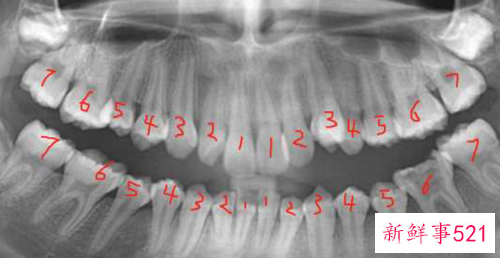

12岁左右,乳牙全部脱落,恒牙全部萌出(不含智齿),此时孩子口内共有恒牙28颗。

18岁左右,若是有智齿,智齿开始陆续萌出,智齿一共四颗,加上四颗智齿的正常人就拥有32颗牙齿。